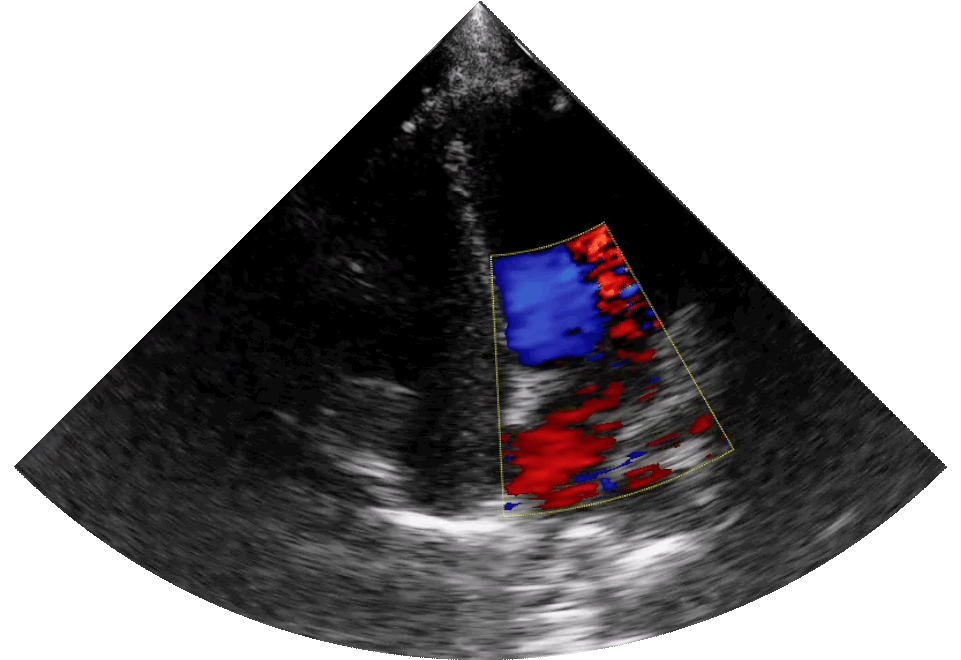

In agriculture, defense, or healthcare, these systems are already revealing hidden insights. Synthetic-aperture radar (SAR) enables drones and satellites to peer through clouds, smoke, or even the earth’s surface. In hospitals, thermal cameras, ultrasound patches, and other electromagnetic sensors provide continuous, non-invasive scanning.

The next generation of ultrasound technology, delivering remote diagnostic imaging. This multispectral “sixth sense” fuses data from different wavelengths into a rich, actionable awareness. ©Sonus Microsystems